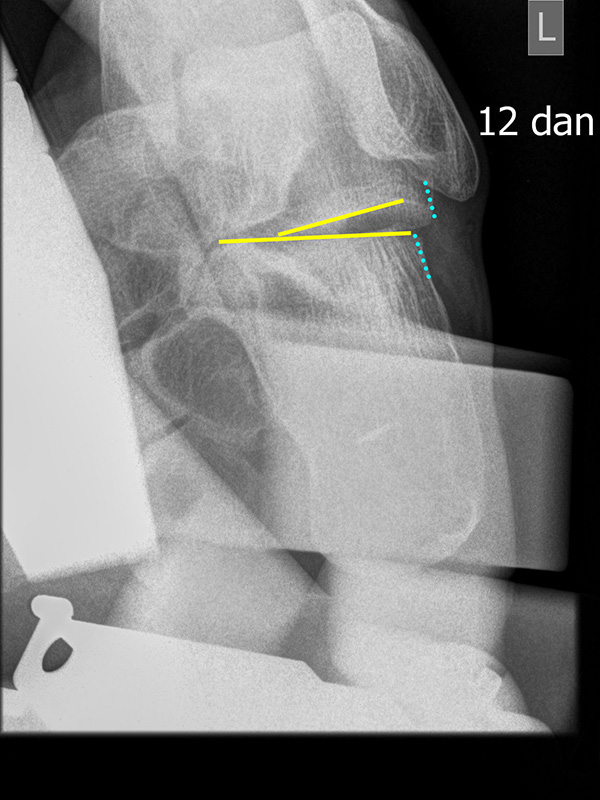

Böhler-Winkel (Syn. Tubergelenkwinkel)

Es wird eine Linie vom Proc. ant. calcanei zur dorsalen Facette des Subtalargelenks gezogen (rot). Die zweite Linie verläuft von der kranialen Begrenzung des Tuber calcanei zum Subtalargelenk (gelb). Gemessen wird der nach dorsal offene Winkel zwischen den beiden Linien (Norm: 22-48° 9).